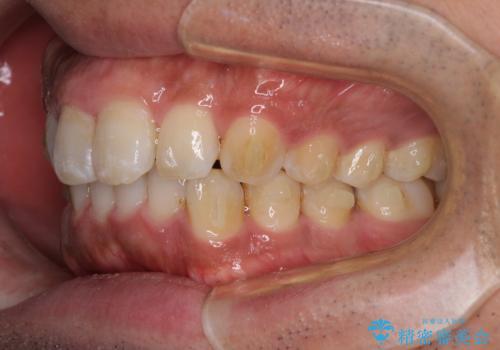

- 上下前歯部の叢生を気にして来院された患者様です。

レントゲン撮影により、右上奥歯が折れていることが分かりました。

患者様自身も何となく違和感を覚えていたとのことで、インプラント補綴治療を行うこととしました。

歯列不正は比較的軽微であったので、インビザラインによる矯正治療とし、矯正治療中にタイミングを見て抜歯とインプラント埋入を行う予定としました。